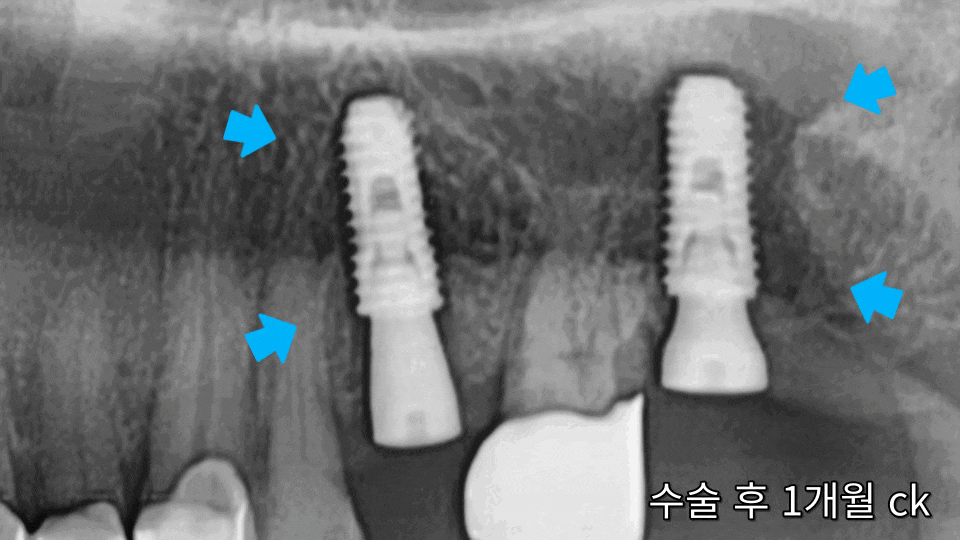

처음에는 1달 후,

그다음에는 약 2달 후로

주변 뼈와 잘 유착되고

흔들리지 않는지를

점검해 주었는데요.

시간이 지날수록

임플란트 주변으로

푸석하던 턱뼈가

점차 단단한 흰색으로

변하고 있습니다.

채워두었던 뼈이식재도

본래의 치조골로

잘 자리를 잡고 있고,

뿌리 끝 주변의

얇은 상악동 막도

깨끗하게 잘 유지되는

모습이네요.^^